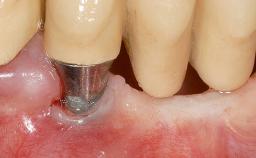

A 30-year-old woman was referred by her general dentist for evaluation of an esthetic complication related to previous implant treatment for congenitally missing maxillary lateral incisors. The patient’s chief complaint was the inadequate esthetic appearance of her smile. The case demonstrates the use of a combined approach to achieve optimal results. Two different flap designs - a tunnel technique and a coronally advanced flap - are employed based on the surgical objectives for the affected site.

Type of Implants Two-Piece

Attachment Two-Piece

Abutment Type Standard

Prosthesis Type FDP